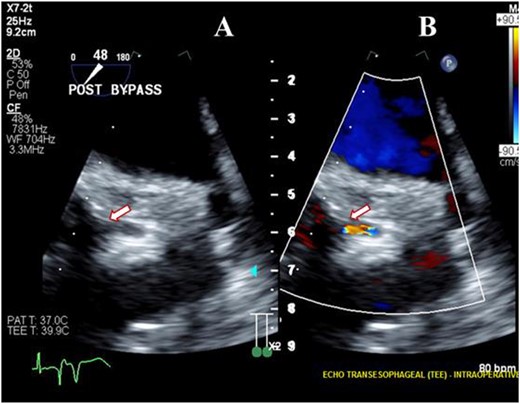

A 56-year-old male underwent AVR for the third time with a 23-mm OnX valve under moderate hypothermic cardioplegic arrest for structural deterioration of bio-prosthetic aortic valve. After suturing the aortic prosthesis, the right coronary artery (RCA) ostium was about 1 cm above, whereas LMCA ostium was relatively close to the prosthesis. Following the removal of aortic cross-clamp, heart resumed activity in ventricular fibrillation and required multiple cardioversions before resuming the sinus rhythm. Subsequently, patient was weaned from CPB on high inotropic support. TEE revealed a well-functioning aortic prosthesis with no paravalvular leak. However, there was severe LV dysfunction with global hypokinesia. The right ventricular function was mildly reduced. A detailed evaluation of the coronary arteries demonstrated severe narrowing of LMCA ostium (Fig. 1A) with turbulent flow (Fig. 1B). A comparison with pre-bypass images confirmed this new finding, whereas RCA caliber and flow were comparable to pre-bypass images.

Transesophageal image following re-operative AVR showing severe stenosis (arrow) at the origin of the left main coronary artery (A) with turbulent flow (arrow) on color Doppler imaging (B).